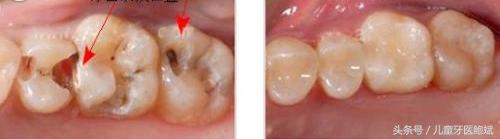

由于塞牙太常见,所以人们往往不会认为塞牙是什么大毛病,不引起重视。实际上,如果你经常塞牙,就应该去看看牙医。几乎所有的龋齿患者都发生过塞牙,其中有一种情况特别难受,就是龋齿发生两颗牙的邻接面,这里有一个龋洞,吃的东西都会塞进去。

牙齿缝隙大给我们带来的困扰,不止是吃饭塞牙,引发负面情绪。口腔不洁是生成蛀牙和牙周病的主要原因,牙缝间的食物残留清理不干净,时间长了,在菌斑的作用下会变坏腐败,造成牙齿邻面龋坏,牙缝变黑。